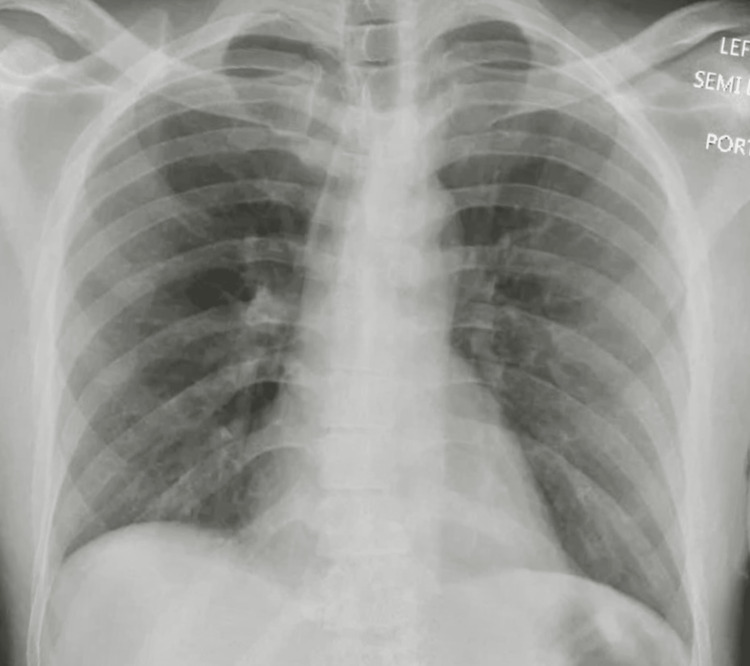

He was started on methylprednisolone IV 250 mg every six hours as the suspicion for a vaping-associated lung injury (VALI) was high. Empiric IV antibiotics were started to cover for any underlying pneumonia, and vancomycin 1 g every 12 hours, IV azithromycin 500 mg OD, and aztreonam 1 g every eight hours in view of the patients’ penicillin allergy were administered. An autoimmune pathology was next on the differential, with possible causes being either primary small vessel vasculitis, primary immune complex-mediated vasculitis, or secondary vasculitis. Hence a vasculitis workup that included glomerular basement membrane (GBM) antibody, antineutrophilic cytoplasmic antibody (ANCA), rheumatoid factor, cyclic citrullinated peptide (CCP) antibody (IgG), antibody to anti scleroderma-70, anti-nuclear antibody, DNA antibody, antibody to Jo-1, and antiphospholipid antibody was done, which came back negative, and IV methylprednisolone was tapered to 62.5 mg every eight hours for four days, followed by 62.5 mg every 12 hours for one more day, and then discontinued, completing a total course of six days. Urine toxicology was also unrevealing, but testing for synthetic cannabinoids could not be performed. Mycobacteria acid-fast bacilli stain was also negative. A repeat chest x-ray done on day six of admission showed an interval resolution of diffuse bilateral airspace opacities (Figure 4), following which the patient was discharged home on no supplemental oxygen. The patient was later followed up in our pulmonary clinic, where he presented in his usual state of health.